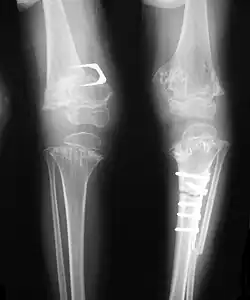

Pseudoachondroplasia. Leg radiographs depicting dysplastic distal femoral and proximal tibial epiphyses, and distal femoral metaphyseal broadening, cupping, irregularities (white arrows) and radiolucent areas especially medially. Note the metaphyseal line of ossification of the proximal tibias (blackarrows) and relative sparing of the tibial shafts. The changes around the knee are known as "rachitic-like changes". Lesions are bilateral and symmetrical.

• Together with rhizomelic limb shortening, the presence of epiphyseal-metaphyseal changes of the long bones is a distinctive radiologic feature of pseudoachondroplasia.

• Dysplastic/hypoplastic epiphyses especially of shoulders and around the knees.

• Metaphyseal broadening, irregularity and metaphyseal line of ossification. These abnormalities that are typically encountered in proximal humerus and around the knees are collectively known as "rachitic-like changes".

• Radiographic lesions of the appendicular skeleton are typically bilateral and symmetric.